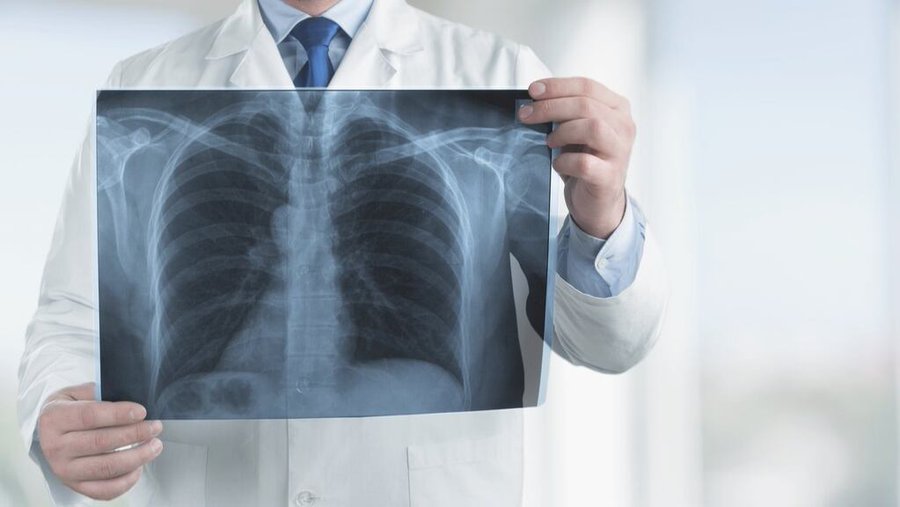

Para confirmar el diagnóstico, se deben realizar distintos estudios médicos. Algunas de las pruebas más utilizadas incluyen:

- Análisis de sangre para descartar otras afecciones.

- Electrocardiograma para evaluar la función cardíaca.

- Ecocardiograma que permite observar el flujo sanguíneo en el corazón.

- Prueba de esfuerzo para analizar la tolerancia del paciente a la actividad física.

- Cateterismo cardíaco derecho, considerado el método más preciso, ya que mide directamente la presión arterial pulmonar.